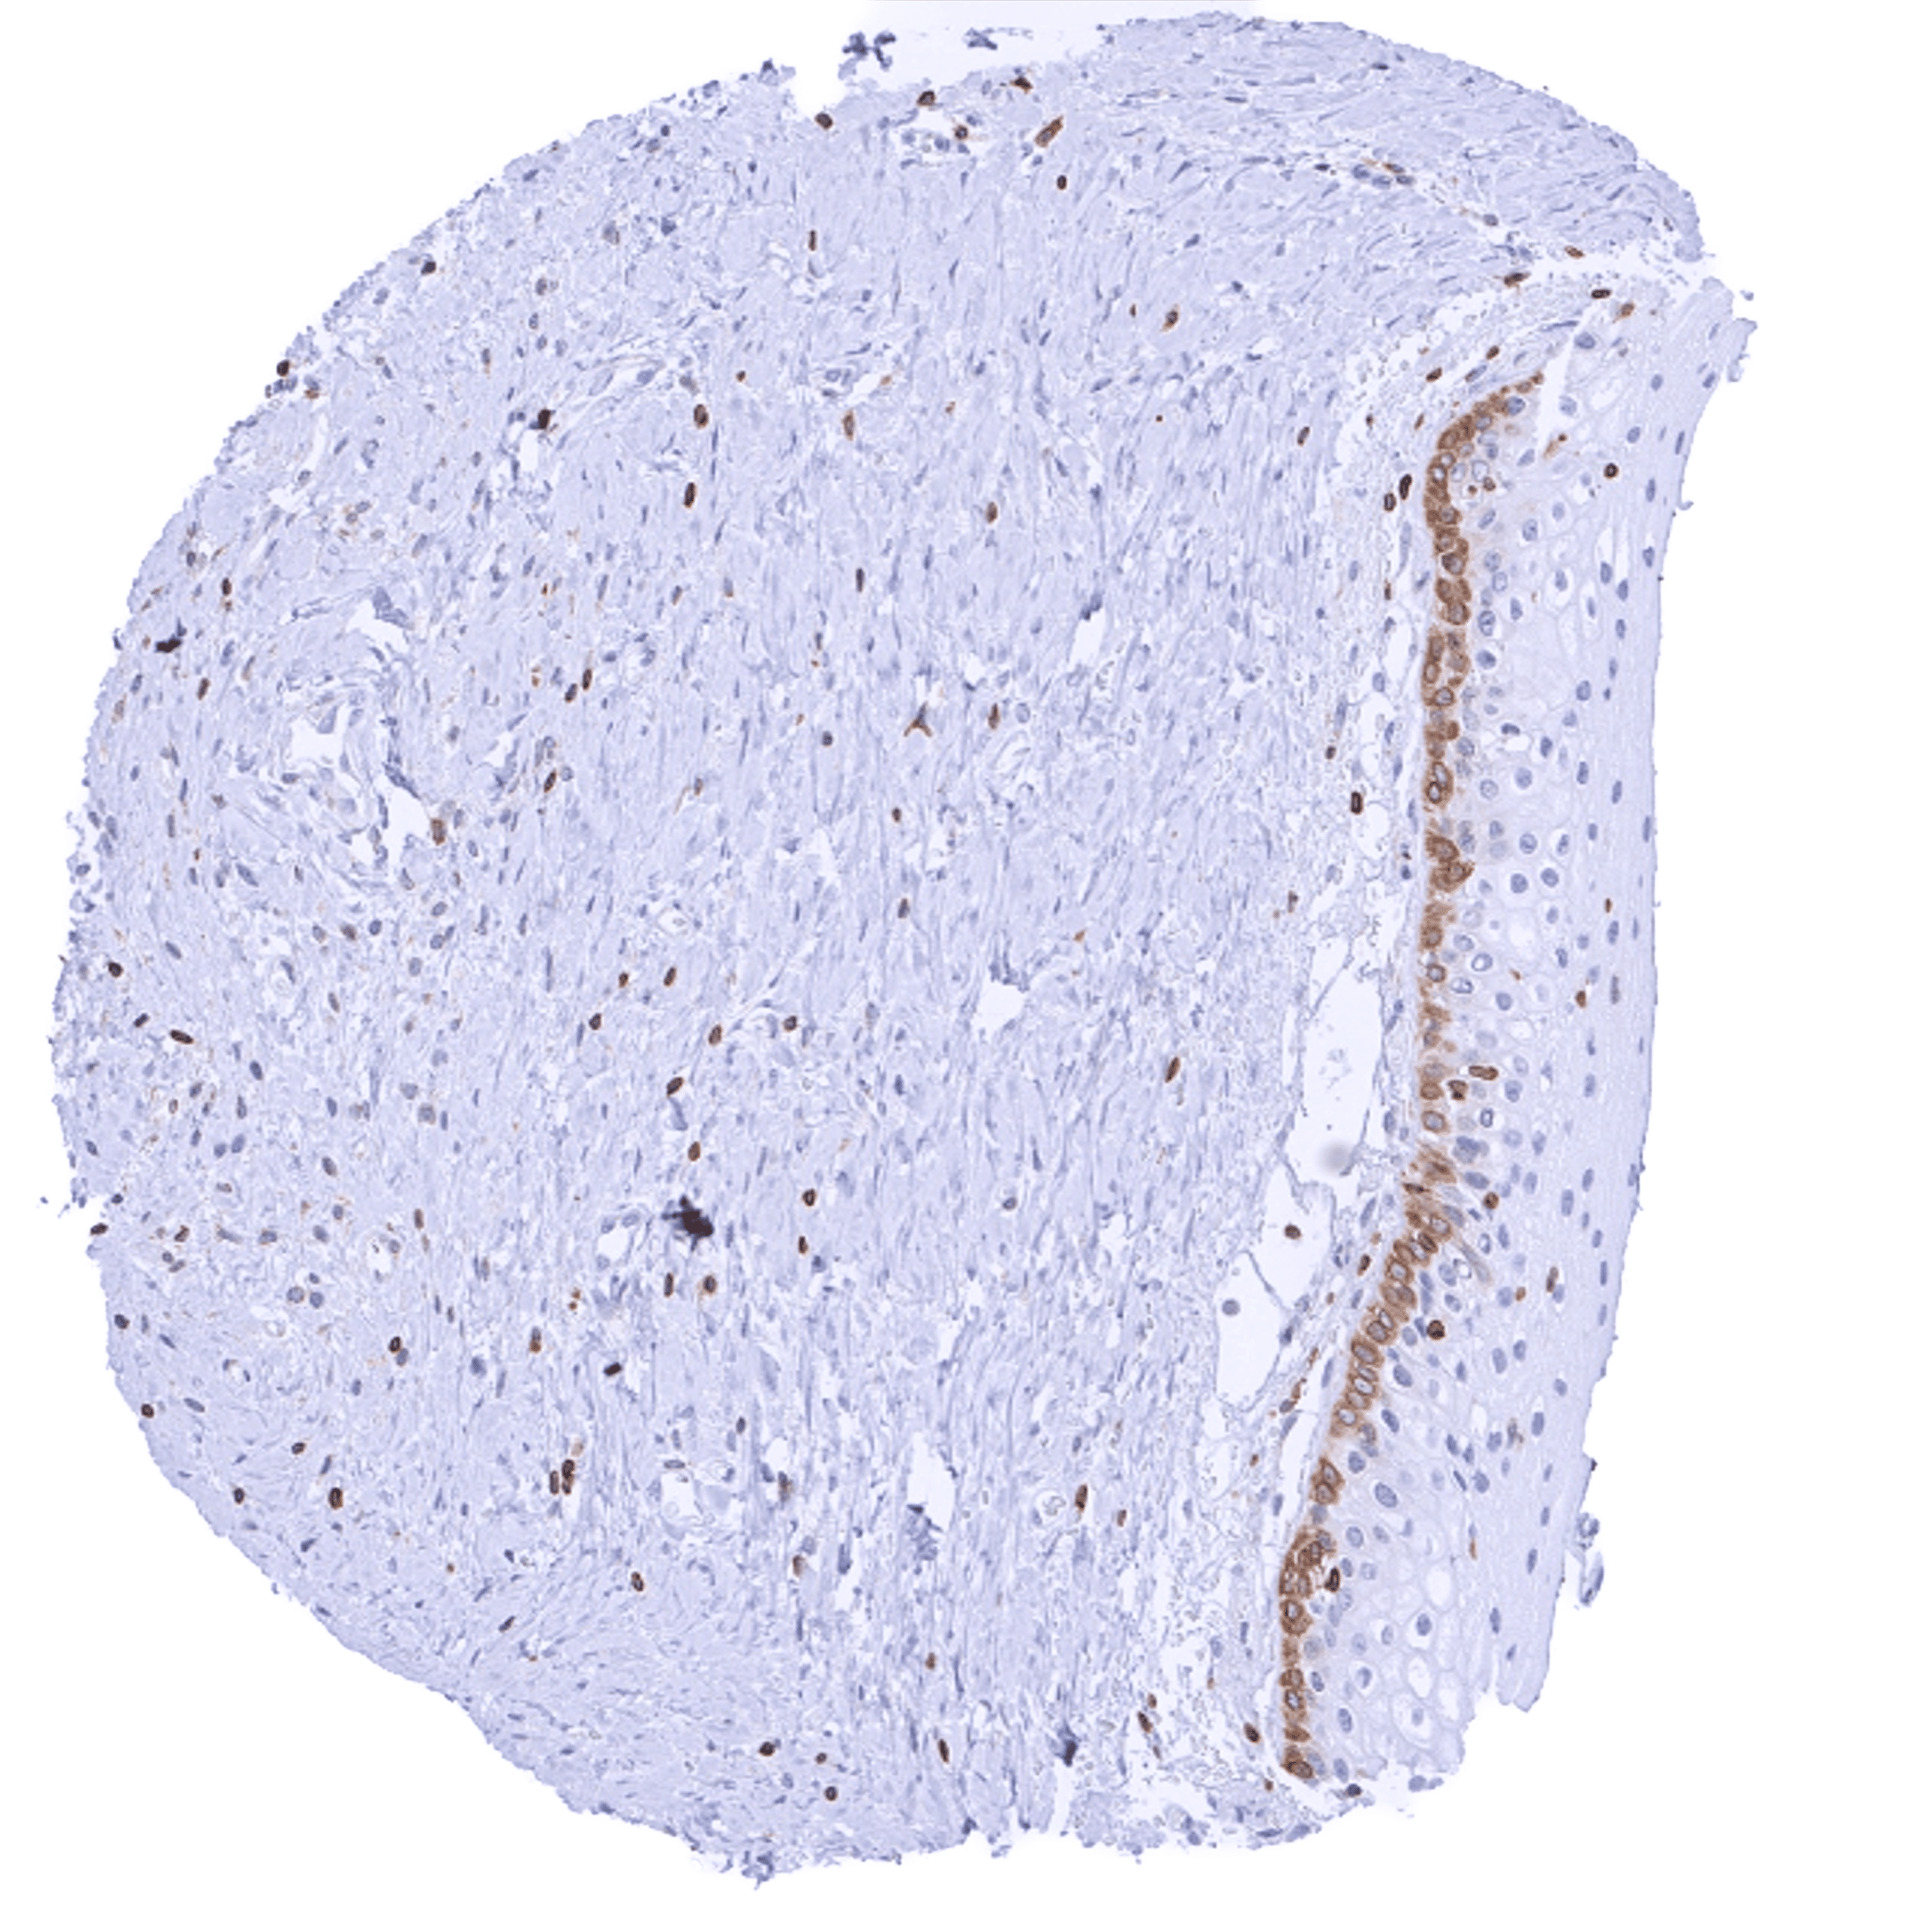

| Uterus, ectocervix | Variable (weak to strong) cytoplasmic bcl-2 staining of basal cells of the squamous epithelium. | |

| Skin | Epidermis | Weak cytoplasmic bcl-2 staining of basal cells of the squamous epithelium. |